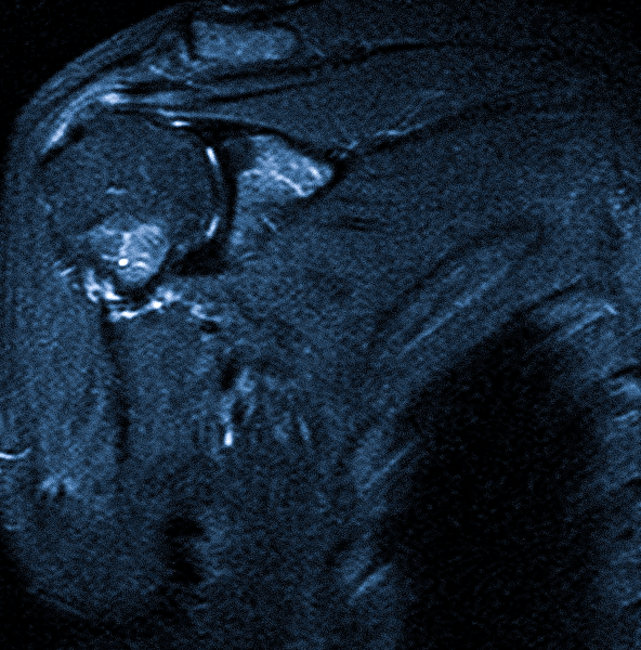

Магнитно-резонансная томография МРТ позволяет визуализировать мягкие ткани тела, используется для диагностики патологических процессов в мышцах, связках, сухожилиях и прилегающих структурах организма.

МРТ мягких тканей помогает врачу, например, выяснить причину компрессии нерва или сосуда. Довольно часто проводится МРТ мягких тканей шеи – для определения патологий глотки, гортани, а также щитовидной железы.

- травматических повреждений (растяжения, разрывы связок и сухожилий)

- воспалительных процессов (инфильтрация тканей, абсцессы, флегмоны)

- дегенеративно-дистрофических изменений

- объемных процессов любой природы.

МР-томография мягких тканей применяется также для обнаружения рентген-неконтрастных инородных тел, гематом, для изучения структурных элементов суставов, лимфатических узлов, сосудистых сплетений.